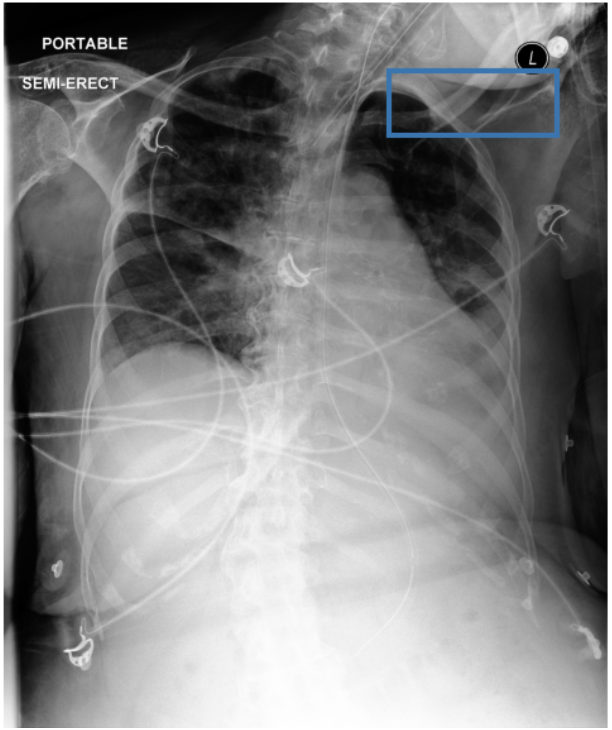

Figure 3 shows phrase grounding results for the phrase “Chronic inflammatory changes predominantly in both lung apices” on an image from PadChest-GR [11]. Both CURE and MAIRA-2 successfully identify the lung apices associated with the described findings. However, CURE’s localization is more accurate and better aligned with the phrase semantics, while MAIRA-2 provides a coarser prediction that only partially covers the relevant areas. As expected, MedGemma-4B-IT does not produce visual grounding outputs, and thus no bounding boxes are shown for this model.